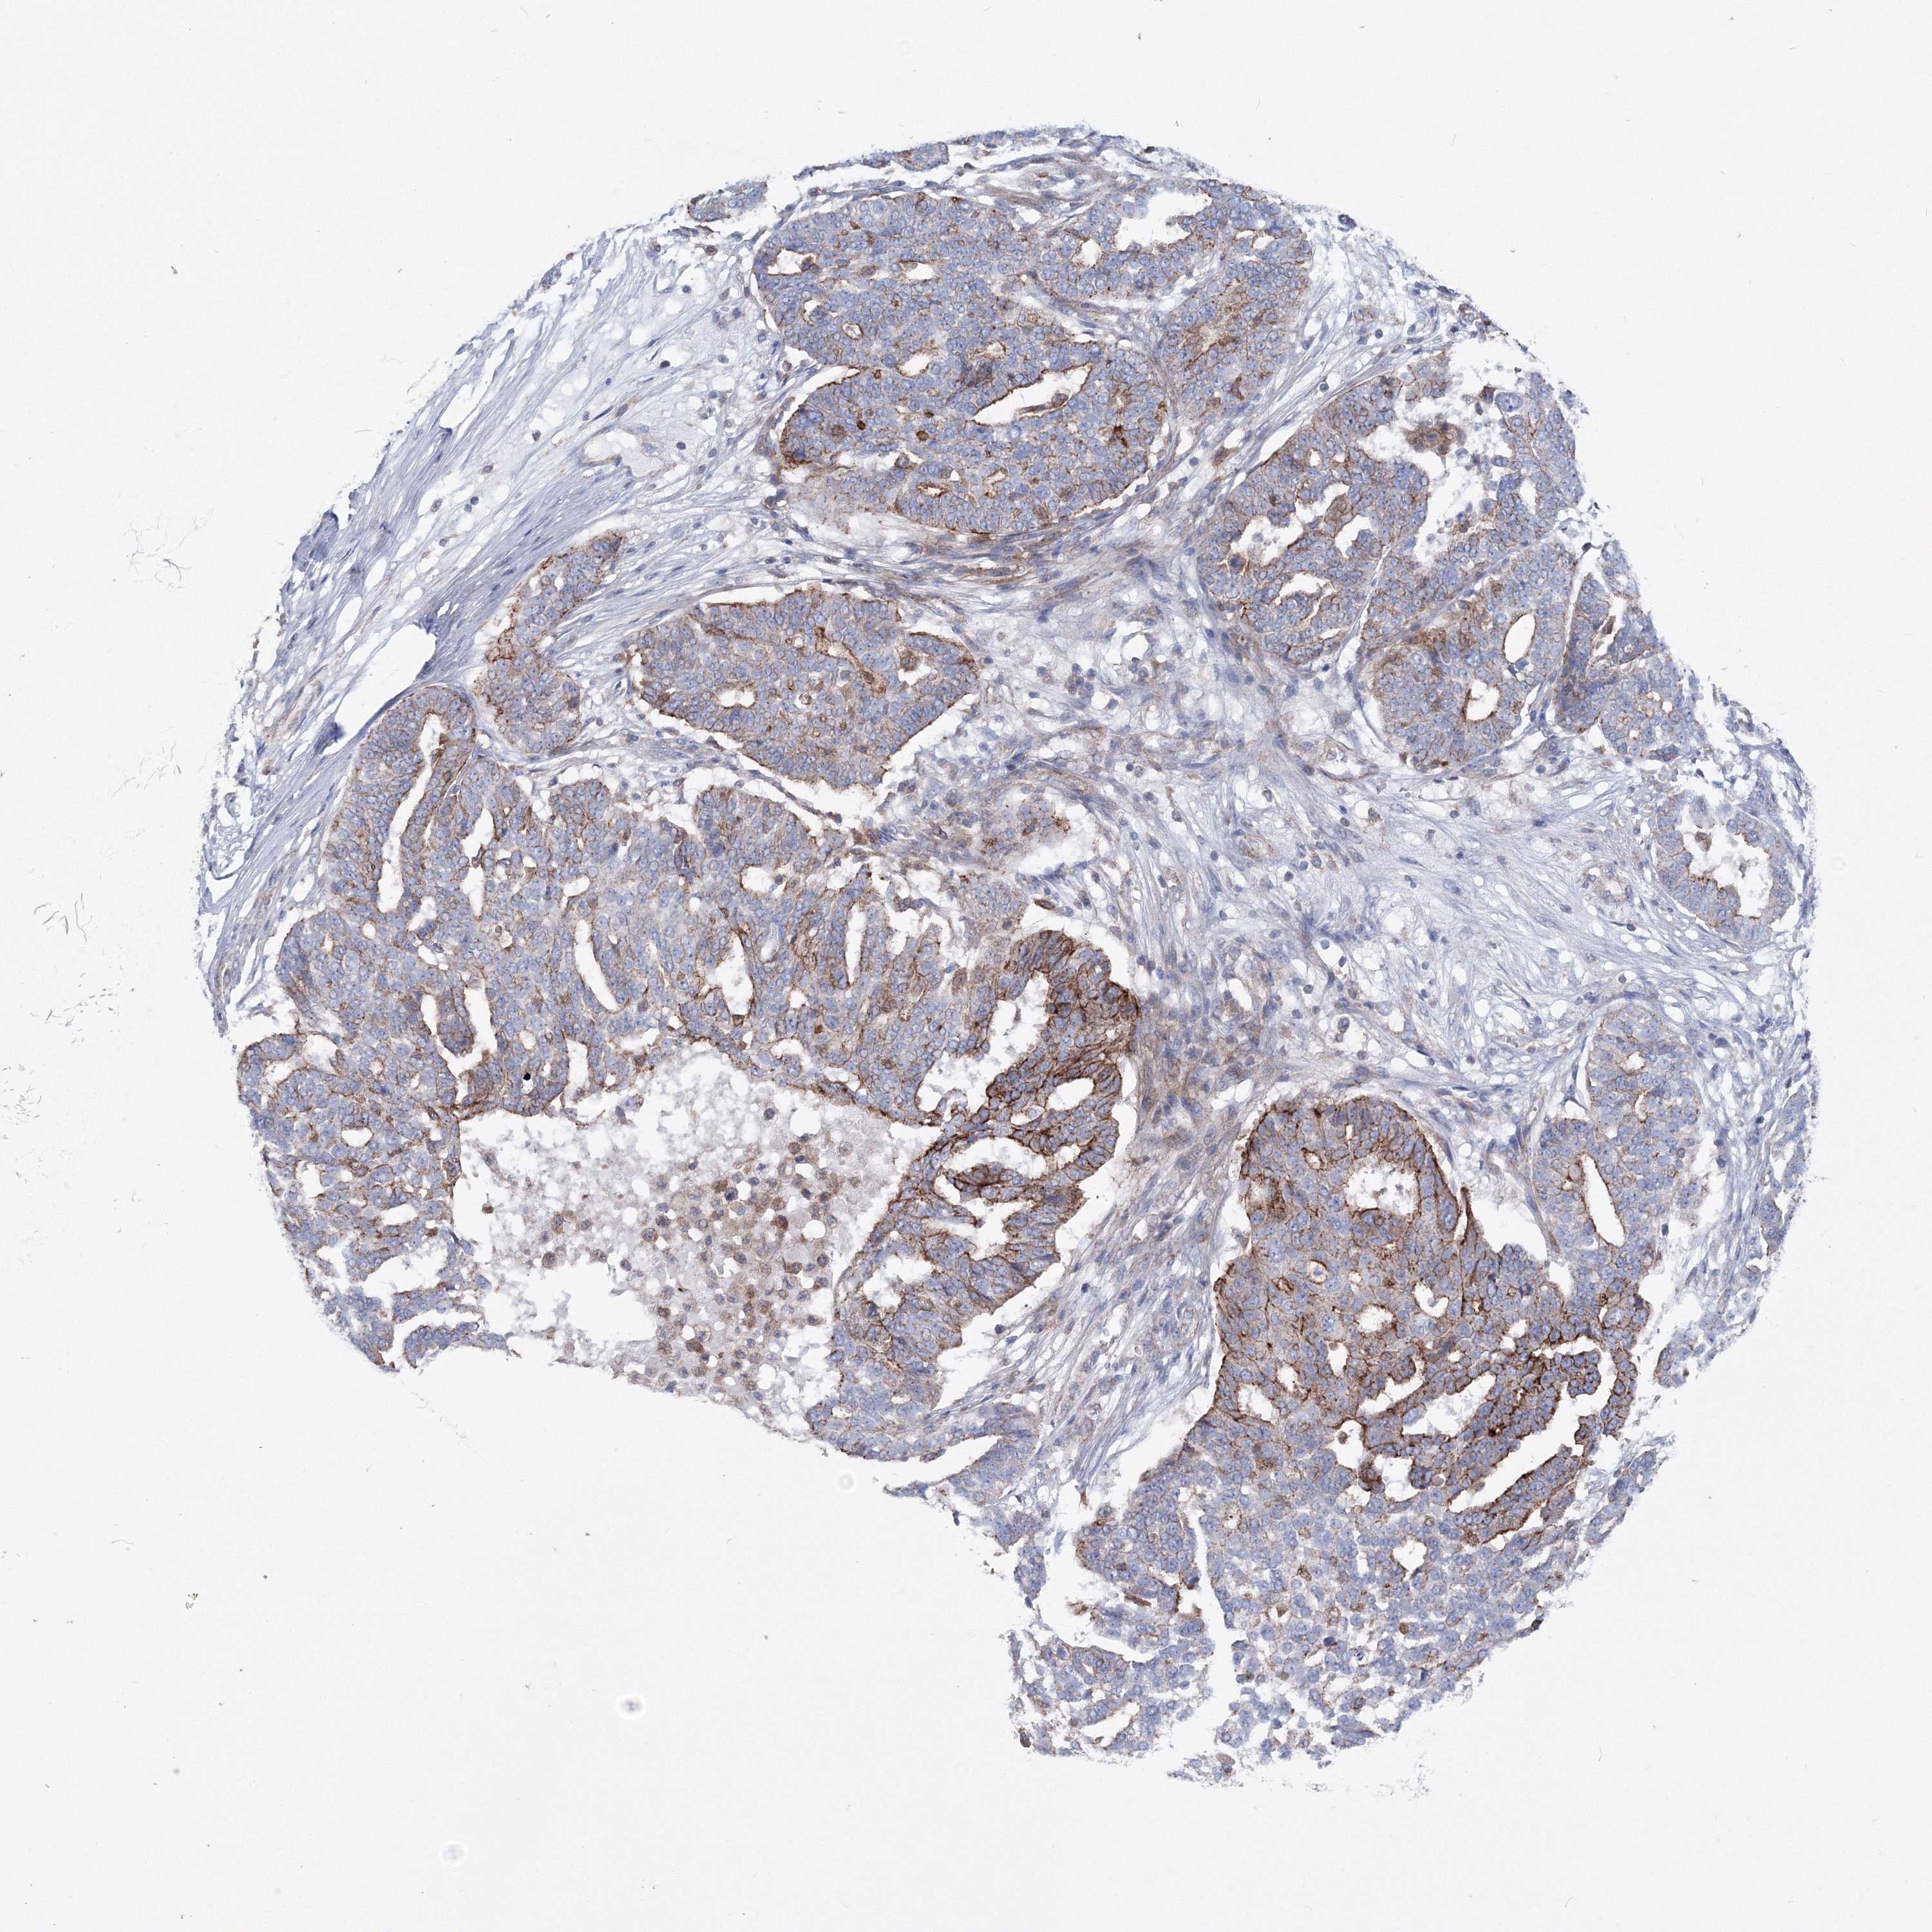

OVARIAN CANCER - Protein expressioni

A mouse-over function shows sample information and annotation data. Click on an image to view it in a full screen mode. Samples can be filtered based on level of antibody staining by selecting one or several of the following categories: high, medium, low and not detected. The assay and annotation is described here.

Note that samples used for immunohistochemistry by the Human Protein Atlas do not correspond to samples in the TCGA dataset.

Antibody stainingi

Antibody staining in the annotated cell types in the current human tissue is reported as not detected, low, medium, or high, based on conventional immunohistochemistry profiling in selected tissues. This score is based on the combination of the staining intensity and fraction of stained cells.

Each image is clickable and will lead to virtual microscopy that enables deeper exploration of all samples and also displays staining intensity scores, fraction scores and subcellular localization as well as patient and tissue information for each sample.

Antibody CAB034422

Staining

High

Medium

Low

Not detected

Intensity

Strong

Moderate

Weak

Negative

Quantity

>75%

75%-25%

<25%

None

Location

Nuclear

Cytoplasmic/membranous

Cytoplasmic/membranous,nuclear

Cystadenocarcinoma, serous, NOS

Carcinoma, endometroid

Cystadenocarcinoma, mucinous, NOS

Carcinoma, NOS